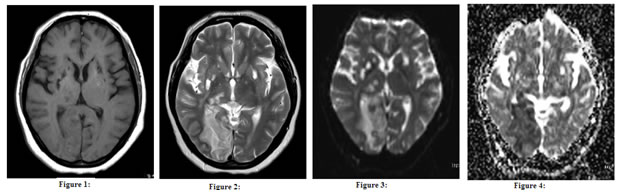

Figure 1: AXIAL T 1WI; Figure 2: AXIAL T2 WI; Figure 3: AXAL DWI; Figure 4: AXIAL ADC MAP

Changes Of Acute Infarct In Right Mca Territory With Changes Of Old Infarct In Bilateral Basal Ganglia (Fig 1 to 4). Of the 10 patients, who showed hyper intensity on DW images, 7 of them presented within 6 hours and 3 within 6 to 12 hours. Lesions were diagnosed on DW MR with 87.5% sensitivity but could not be detected on T2W MR when duration of symptoms was within 6 hours. Lesions were diagnosed on DW MR with sensitivity of 100% and on T2W MR with sensitivity of 72.73% when duration of symptoms was 6 to 12 hours. However, T2W MR Images were equally sensitive (100% sensitivity) as DW MR as the duration of symptoms increased beyond 12 hours. DW MRI is particularly sensitive for detection of acute ischemic stroke. A total of 50 patients having infarcts were studied in this group. The sensitivity of DW imaging was 87.5% within initial 6 hours and 100% above 6 hours. The sensitivity of T2W imaging was 0% and 72.73% within the initial 6 hours and 6 to 12 hours respectively, reaching 100% above 12 hours. The results of the present study correlated with the study done by Gonzalez RG et al10